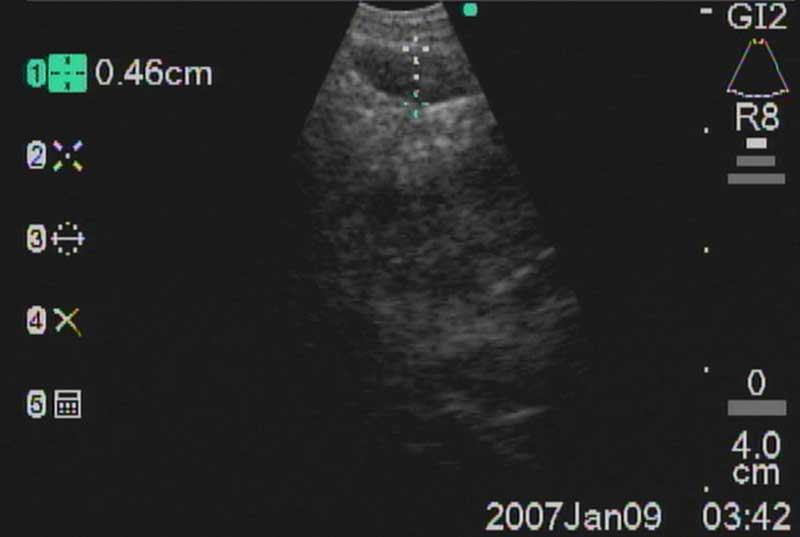

The easiest place to start ultrasound imaging is generally the right main bronchus and subcarinal areas. Pass the scope to the right side of the carina with the probe facing anteriorly and apply to the anterior wall of the RMB. This will bring into view the right main pulmonary artery. Vascular structures appear hypoechoic and pulsatile, and are usually readily discernable without using the color Doppler. If doubt persists flow within can be confirmed by switching to the Doppler overlay (B/CPD; Figures 5 and 6). Turn the scope 90 degrees counter-clockwise. This allows visualization of the subcarinal area from the right side. By moving the scope in and out the level 7 subcarinal node can usually be identified. If not, repeat this procedure in the LMB turning the scope 90 degrees clockwise instead. Once the subcarinal nodes are visualized it is relatively easy to identify other landmarks, by correlating anatomical location with the ultrasound image. It is useful to attempt to map out all nodes that you wish to biopsy first, before needle tract bleeding confounds the fiber optic image. The size of the node can be measured by freezing the US image [Freeze] and using the [Measure/Select] button and cursor scroll ball (Figures 5 and 7).